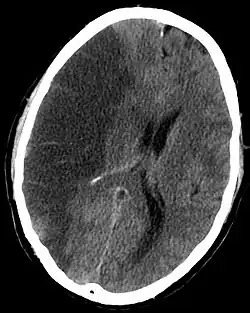

A stroke can be caused by a few different situations, but the basic result is the same. Blood flow to a section of the brain is stopped, which results in rapid depletion of oxygen and other nutrients in the starved section. The starved section of brain tissue quickly begins to die, and results in a lesion in the brain. The resulting lesion can be traced loss of various cognitive functions depending on the location and area of damage.[5]